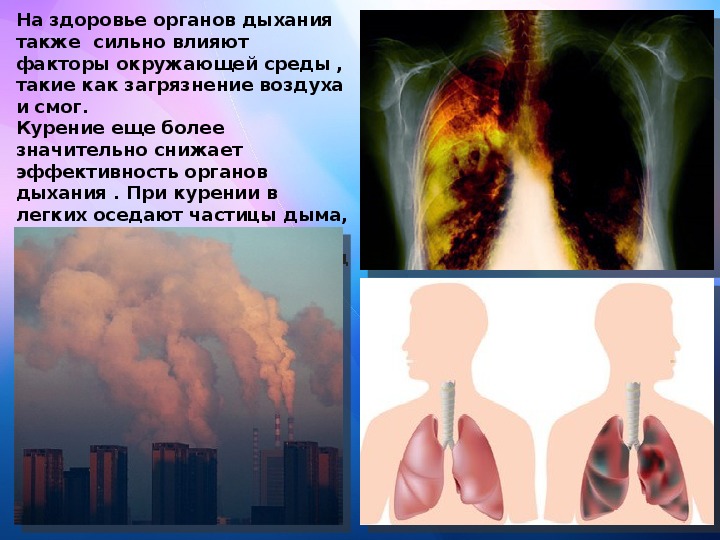

Здоровый образ жизни: Влияние курения